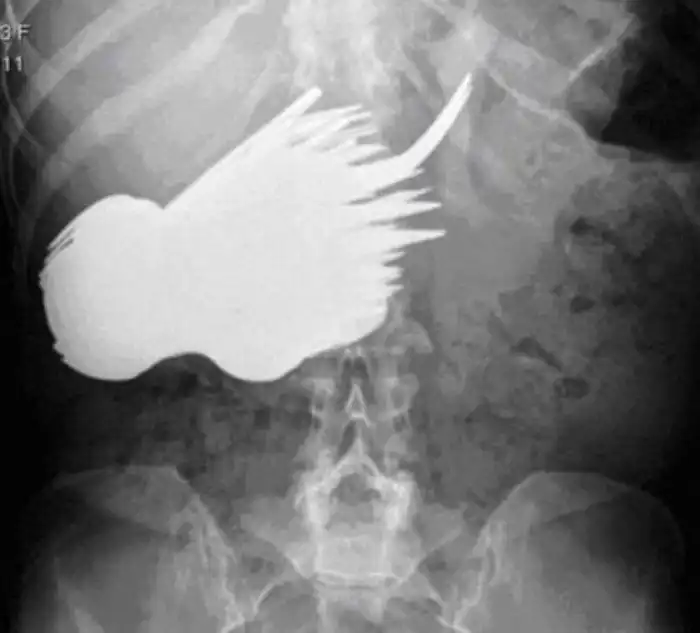

Мужчина из Китая жаловался на боли в желудке. Мужчине пришлось обратиться к врачам после того, как он не смог извлечь бутылки при помощи закрученного куска проволоки. Когда медицинские работники спрашивали его о боли, он утверждал, что не понимает, из-за чего он испытывает дискомфорт. Однако память ему вдруг вернулась, когда врачи показали рентгеновские снимки бутылки и проволоки внутри него. Он подтвердил, что вставил бутылку дома после чего, она застряла, и сказал, что при помощи стальной проволоки попытался вытащить бутылку в приступе паники.